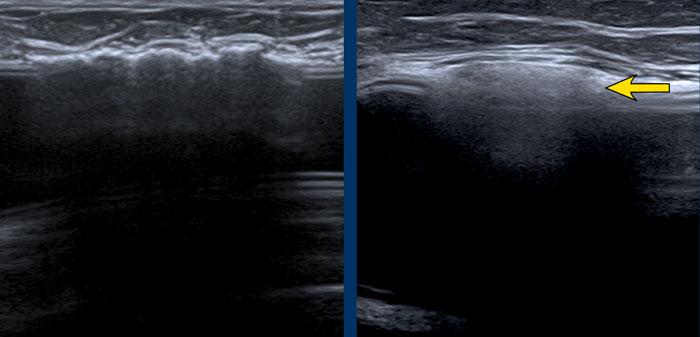

A. Không còn nhìn thấy vỏ bọc xung quanh bề mặt túi độn. Nội dung bên trong hoàn toàn không đồng nhất và thoái hóa.

B. Vỏ bọc bị xẹp (mũi tên vàng) và không đi theo phức hợp vỏ bọc-bao xơ bên ngoài (mũi tên trắng).

Có một khối tập hợp không đồng nhất chứa Silicone nằm giữa vỏ bọc và bao xơ.